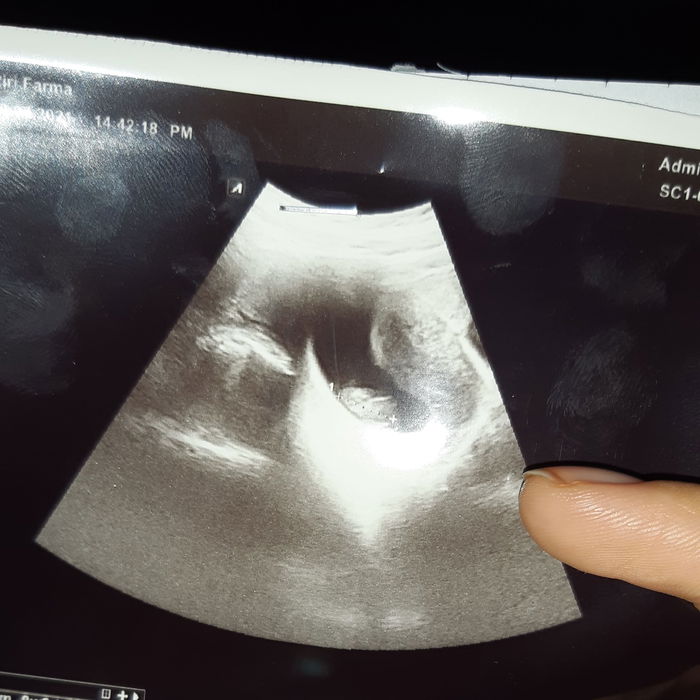

Berkali-kali aku membaca kembali petunjuk yang ada di bungkus testpack ternyata sudah sesuai kalau hasilnya positif. Aku sangat bahagia. Tapi agar lebih yakin seminggu kemudian aku USG dan memang sudah terdapat kantong kehamilan usianya sudah 5 minggu.

Namun sebulan kemudian aku mulai sering ngeflek coklat aku kira ini hal wajar. Tapi semakin hari semakin banyak. Aku cari-cari digoogle tetapi semua mengarah ke tanda keguguran. Pikiranku mulai tidak tenang dan aku segera USG kembali ternyata usia kehamilanku berhenti berkembang di usia 9 minggu, detak jantung janin tidak ada lagi. Hatiku sangat hancur.

Sebulan setelah kuret aku tidak haid namun setelah bulan kedua aku mulai haid kembali. Setelah memasuki bulan ketiga aku tidak haid aku pikir ini cuma karena hormon. Tapi sudah hampir dua minggu aku telat dan ini tidak seperti biasanya. Aku menyuruh suami membeli testpack dan ternyata benar aku positif kembali. Hanya dalam jangka dua bulan setelah keguguran. Tergolong cepat menurutku. Tapi aku sangat bersyukur namun di sisi lain masih trauma. Takut gagal lagi menjaga kehamilan ini.

Tapi, aku tidak peduli perkataan orang, mereka tidak bisa seenaknya memprediksi kehamilan seseorang. Bagiku selama aku rajin periksa dan USG dan semua hasilnya normal aku juga rajin makan dan minum vitamin. Aku sama sekali tidak khawatir. Selama kehamilan kan sang ibu juga harus bahagia dan tidak boleh stres.